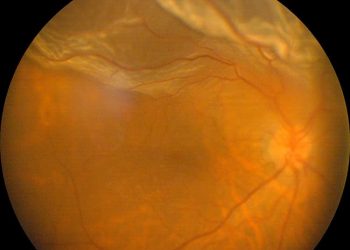

Distacco di Retina